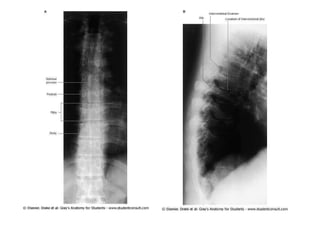

Radiograph of lumbosacral spina bifida. There is an absence

of laminae and spinous processes in the lumbosacral region.